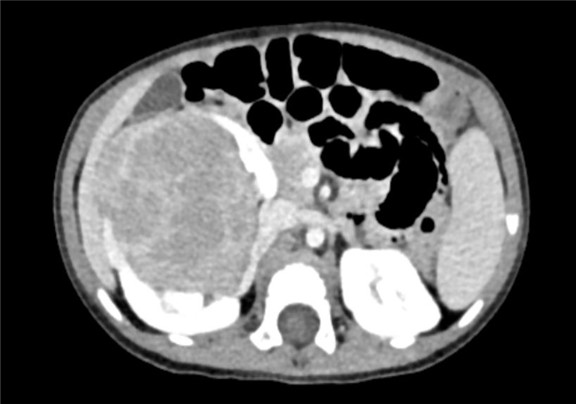

下腹部CT动态增强扫描 肾母细胞瘤化疗后,右肾巨大占位,较前范围减小,请结合临床。

术前CT检查:

动脉期

静脉期

平衡期